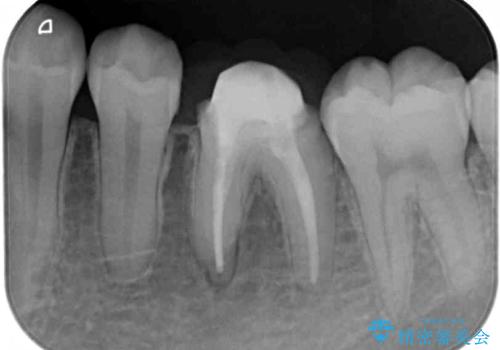

- 食事の度にクラウンにこびりつくとのことで来院された患者様です。

以前の医院では治療終了と言われたそうですが、即席で製作した仮歯が装着された状態でした。

患者様と相談し、根管治療を再度行った後、フルジルコニアクラウンにて補綴治療することとしました。